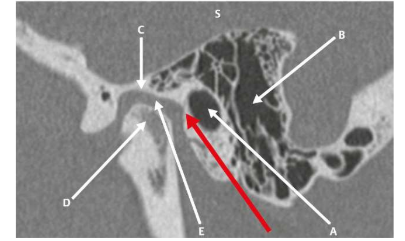

A orelha externa é a parte visível sendo composta pelo pavilhão auricular e pelo conduto auditivo externo, (CAE). O pavilhão auricular é composto por cartilagem, recoberto por pele e é responsável pela captação do som e seu direcionamento para o canal auditivo externo. Ilustração em janelamento ósseo auricular.

Fonte: Pauna, Henrique, F. et al. Avaliação do Osso Temporal por Imagem: Uma Abordagem Radiológica e Histológica., Thieme Brazil, 2024.

De acordo com a ilustração, assinale a alternativa incorreta.